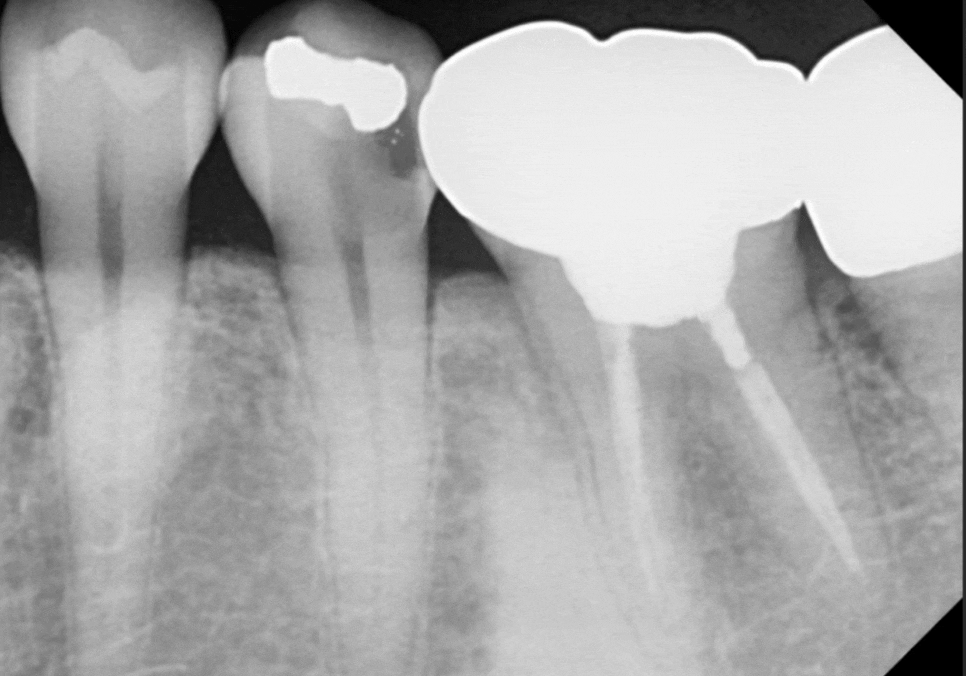

하지만 정밀 검사를 해보니

상황은 생각보다 심각했습니다.

아말감 아래로 2차 충치가

아주 깊게 진행되어 있었거든요.

다행히 뿌리 쪽에 염증은 보이지 않아서,

신경치료를 하고 크라운을 씌워

다시 한번 튼튼하게 써보실 수 있도록

환자분과 충분히 상의를 했었는데요.

다만, 치아가 부러질 때의 충격 때문에

뿌리 쪽에 눈에 보이지 않는

'미세한 금(Crack)'이 갔을 가능성도 있어서,

그 부분에 대해 꼼꼼히 설명해 드렸습니다.